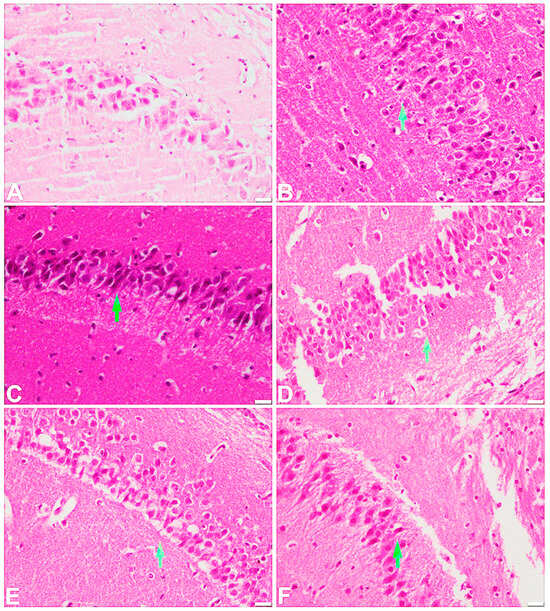

2.6. Effect of the Test Compound on the Histopathological Examination of the Frontal Cortex and Hippocampus

| Frontal Cortex Region | |||||

|---|---|---|---|---|---|

| S. No. | Group | Degeneration Process | Plaques/Fibrosis | ||

| Pyknosis | Karyolysis | Vacuolation | |||

| 1 | Vehicle group | No | No | No | No |

| 2 | Scopolamine | Yes | Yes | Yes | Yes |

| 3 | Scopolamine + donepezil | No | No | Yes | No |

| 4 | T15 + scopolamine | Yes | Yes | Yes | No |

| 5 | T30 + scopolamine | No | No | Yes | Yes |

| 6 | T45 + scopolamine | No | No | Yes | No |